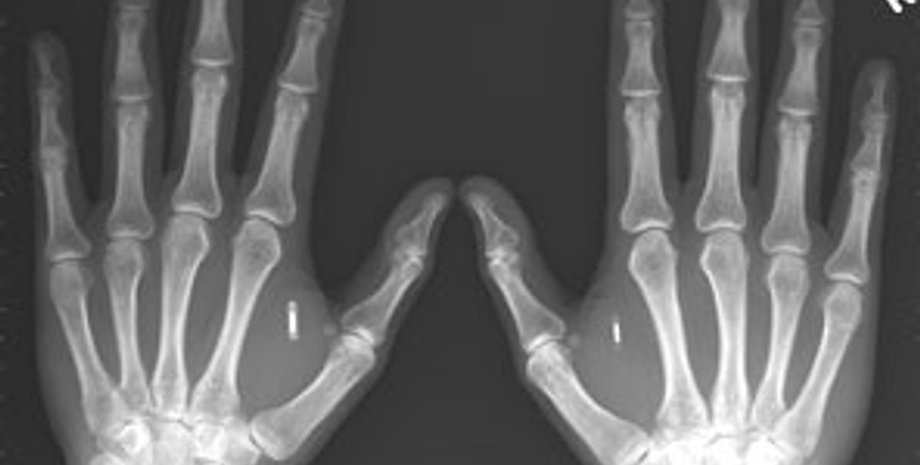

Команда немецких хирургов провела первую в стране операцию по двойной пересадке донорских рук 54-летнему пациенту. В операции, продолжавшейся более 16 часов, принимали участие пять групп врачей общей численностью 30 человек.

Пациент немецких врачей лишился рук много лет назад, в результате несчастного случая на сельскохозяйственных работах. Донором рук стал 19-летний молодой человек, погибший в автокатастрофе. Операция, подготовка к которой заняла около пяти лет, состоялась в пятницу в мюнхенской клинике Исар.

Участники многочасовой операции были разделены на пять групп: по две группы были заняты одновременной пересадкой верхних конечностей, еще одна занималась изъятием сосудов донора, пересадка которых должна обеспечить кровоснабжение пересаженных конечностей.